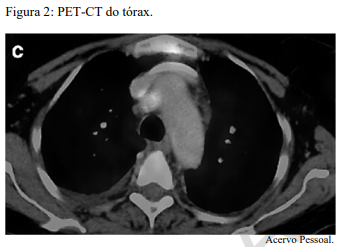

Um paciente de 62 anos de idade, tabagista ativo, cerca de 180 anos-maço, queixa-se de cansaço, tosse seca e perda de peso; por isso, procurou atendimento médico. O paciente referiu que pesava 100 kg e perdeu 10 kg. Realizou-se tomografia computadorizada de tórax, com evidência de lesão sólida de 2,1 cm em topografia de lobo inferior à direita, sólida, espiculada, com margens bem definidas e densidade de partes moles, assim como linfonodomegalia paratraqueal direita de 1,5 cm, paratraqueal esquerda de 1,2 cm e subcarinal de 2 cm. O paciente foi submetido a PET-CT de corpo inteiro, com evidência de hipercaptação de radiofármaco pela lesão (SUV 12) e eplo linfonodo representado na figura 2 a seguir.

Com base nesse caso clínico, nas imagens apresentadas e nos conhecimentos médicos correlatos, julgue o item a seguir.

O paciente tem indicação, nesse momento, de lobectomia superior direita por VATS, com linfadenectomia mediastinal.